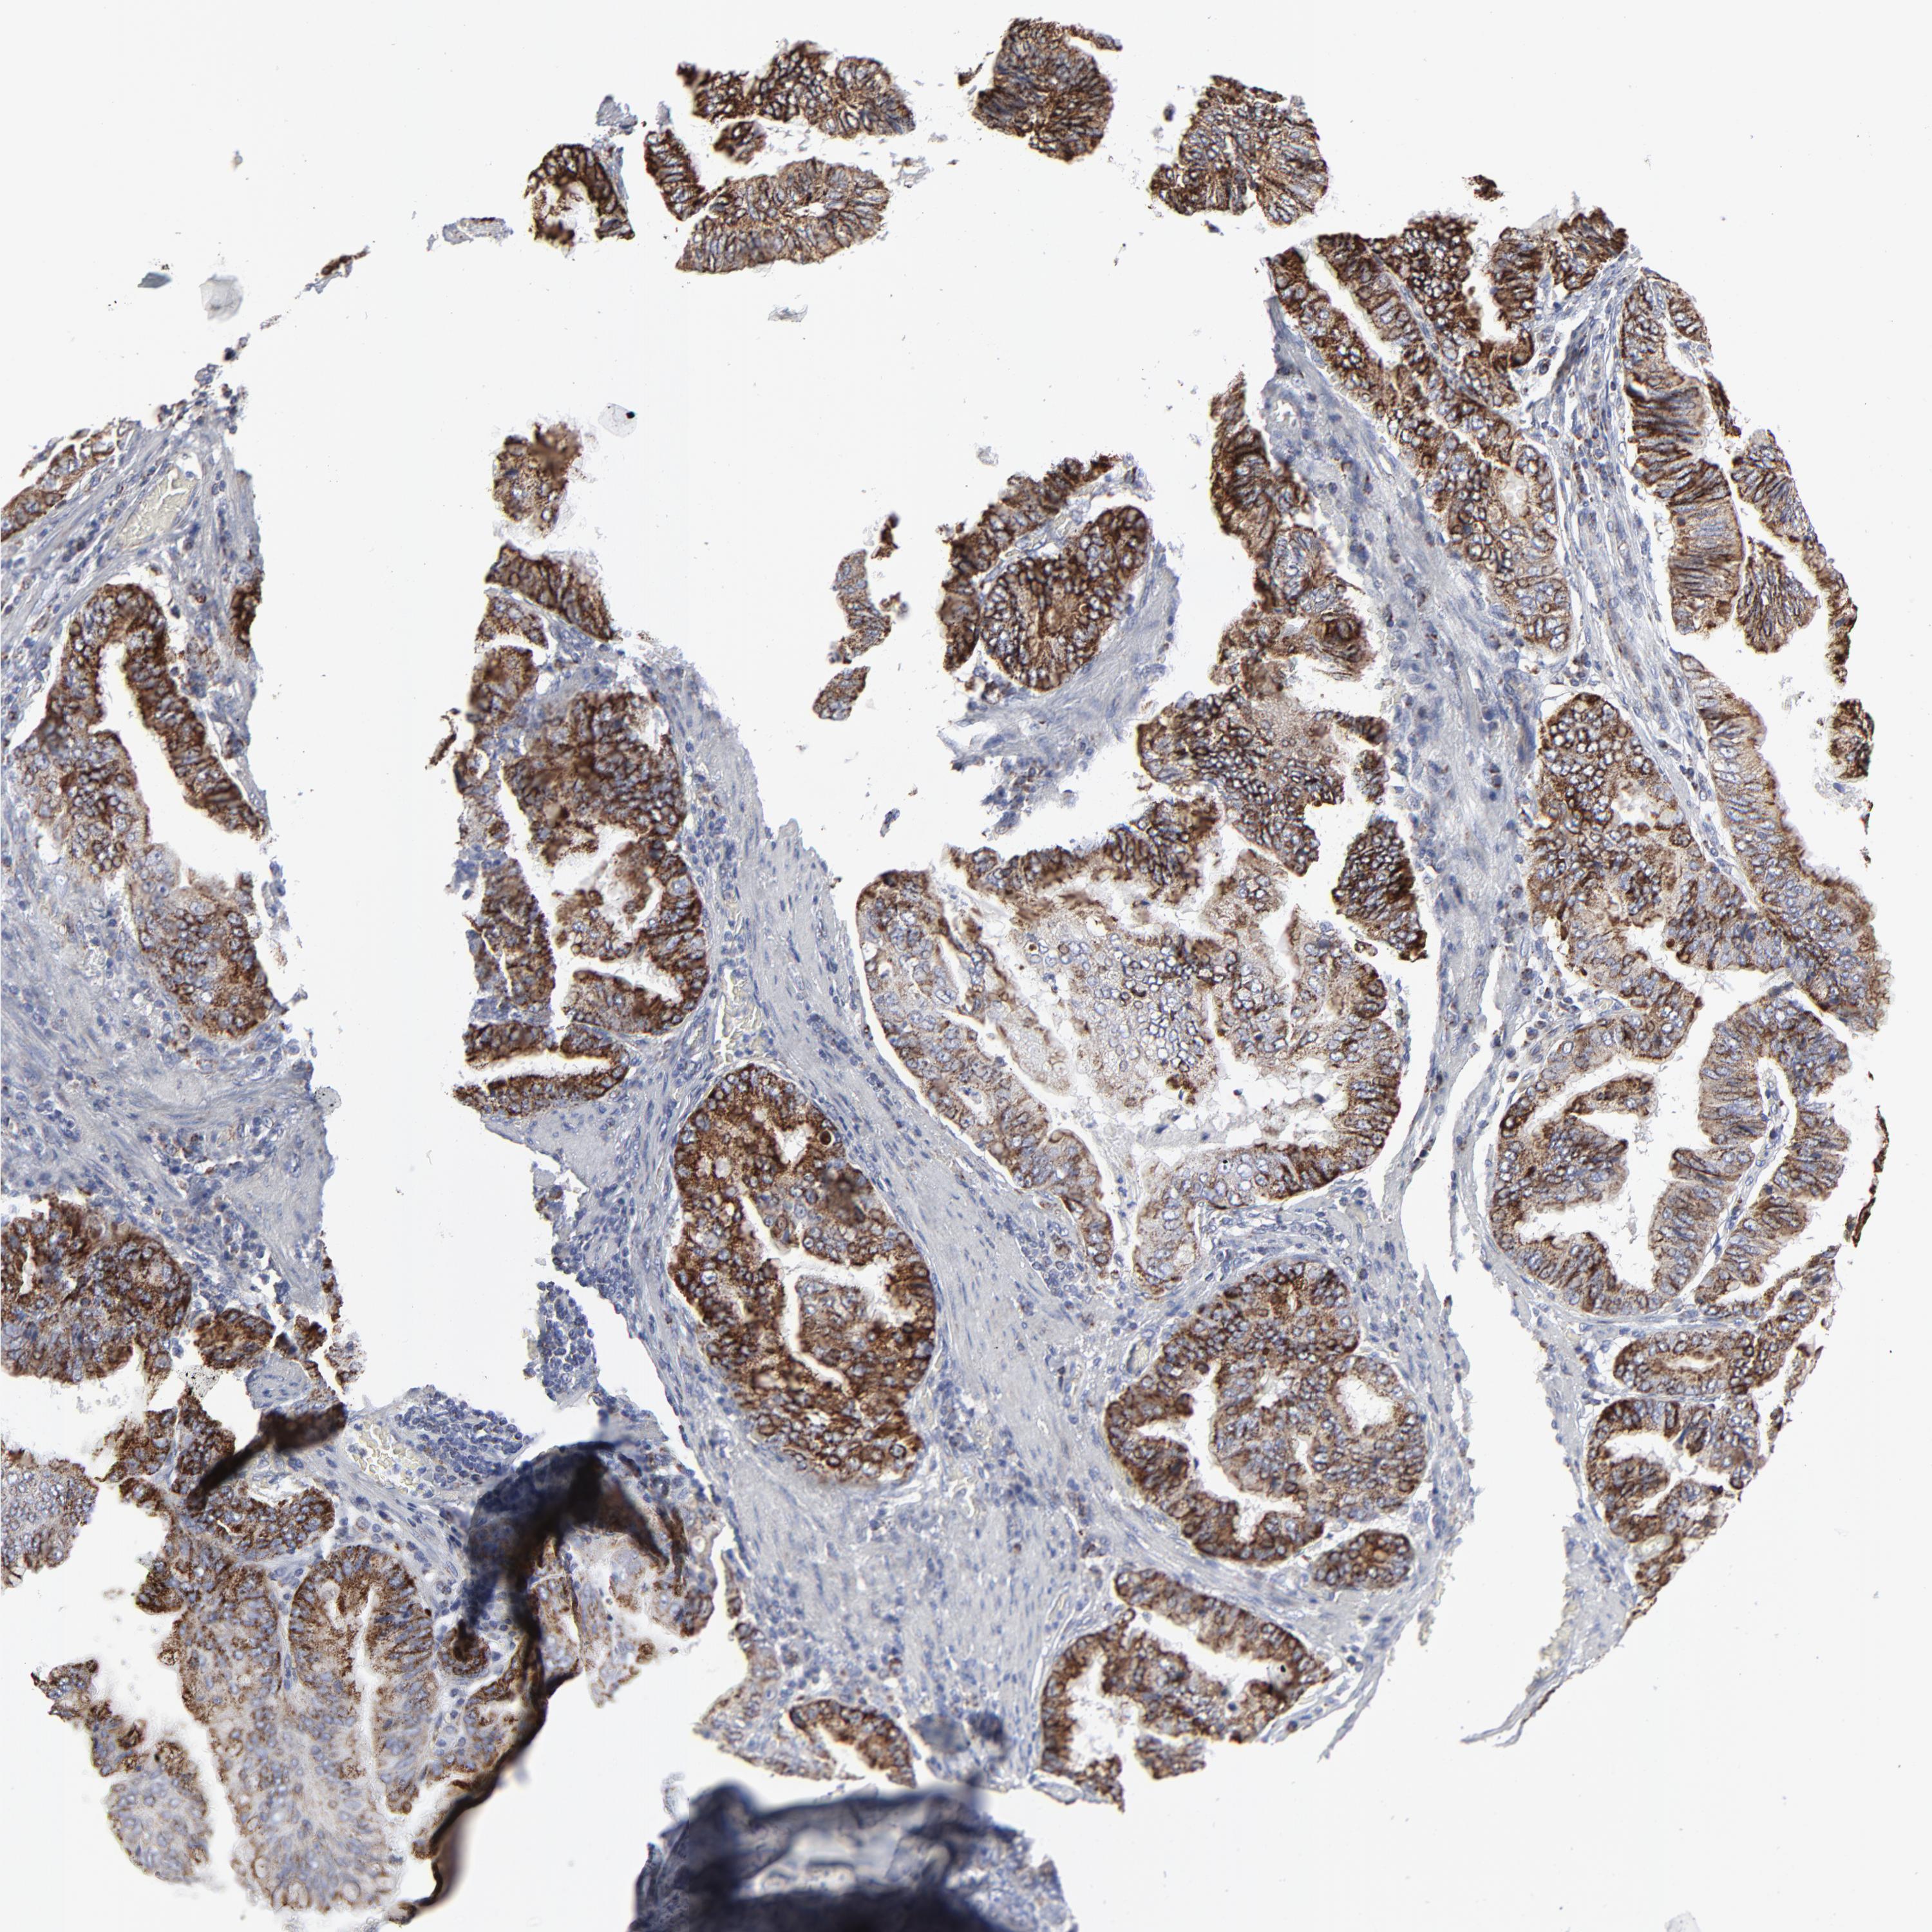

STOMACH CANCER - Protein expressioni

A mouse-over function shows sample information and annotation data. Click on an image to view it in a full screen mode. Samples can be filtered based on level of antibody staining by selecting one or several of the following categories: high, medium, low and not detected. The assay and annotation is described here.

Antibody stainingi

Antibody staining in the annotated cell types in the current human tissue is reported as not detected, low, medium, or high, based on conventional immunohistochemistry profiling in selected tissues. This score is based on the combination of the staining intensity and fraction of stained cells.

Each image is clickable and will lead to virtual microscopy that enables deeper exploration of all samples and also displays staining intensity scores, fraction scores and subcellular localization as well as patient and tissue information for each sample.

Antibody HPA003323

Antibody CAB002007

Staining

High

Medium

Low

Not detected

Intensity

Strong

Moderate

Weak

Negative

Quantity

>75%

75%-25%

<25%

None

Location

Nuclear

Cytoplasmic/membranous

Cytoplasmic/membranous,nuclear

Adenocarcinoma, NOS